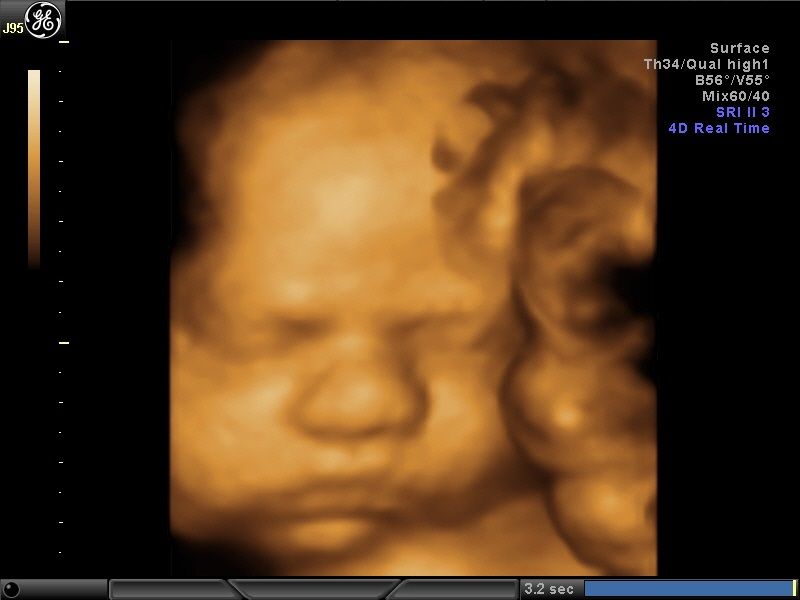

Wykonuję tam około 600 badań „I trymestru ciąży” rocznie, co daje łącznie około 1200 badań z „II trymestrem ciąży” włącznie. Od 15 lat w swoim gabinecie również wykonuję badania prenatalne I, II i III trymestru ciąży w znacznej ilości. To umożliwia mi osiągnięcie doskonałych wyników w diagnostyce tych badań, co stawia mnie w czołówce specjalistów diagnostyki prenatalnej.

Większość swojej kariery zawodowej spędziłem na sali porodowej oraz patologii ciąży. Aktualnie pracuję na sali porodowej. Mam 15-letnie doświadczenie w diagnostyce prenatalnej poparte dużą ilością przebadanych pacjentek i posiadam najszerszy wachlarz certyfikatów z zakresu ultrasonografii płodowej. Corocznie uczestniczę w szkoleniach i kursach ultrasonograficznych.

- diagnostyka prenatalna I,II i III trymestru ciąży z przepływami dopplerowskimi, testem podwójnym (PAPPA i B-HCG), oznaczanie DNA płodowego NIPTY, testy SANCO, NIFTY, VERACITY